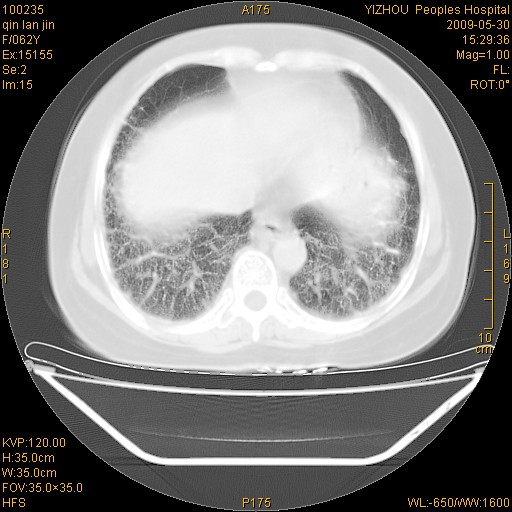

弥漫性双肺间质纤维化。

两肺弥漫性间质性病变(间质性肺炎伴肺间质纤维化?)。

弥漫性双肺间质纤维化

支持弥漫性肺间质纤维化。

间质性肺炎伴肺间质纤维化。